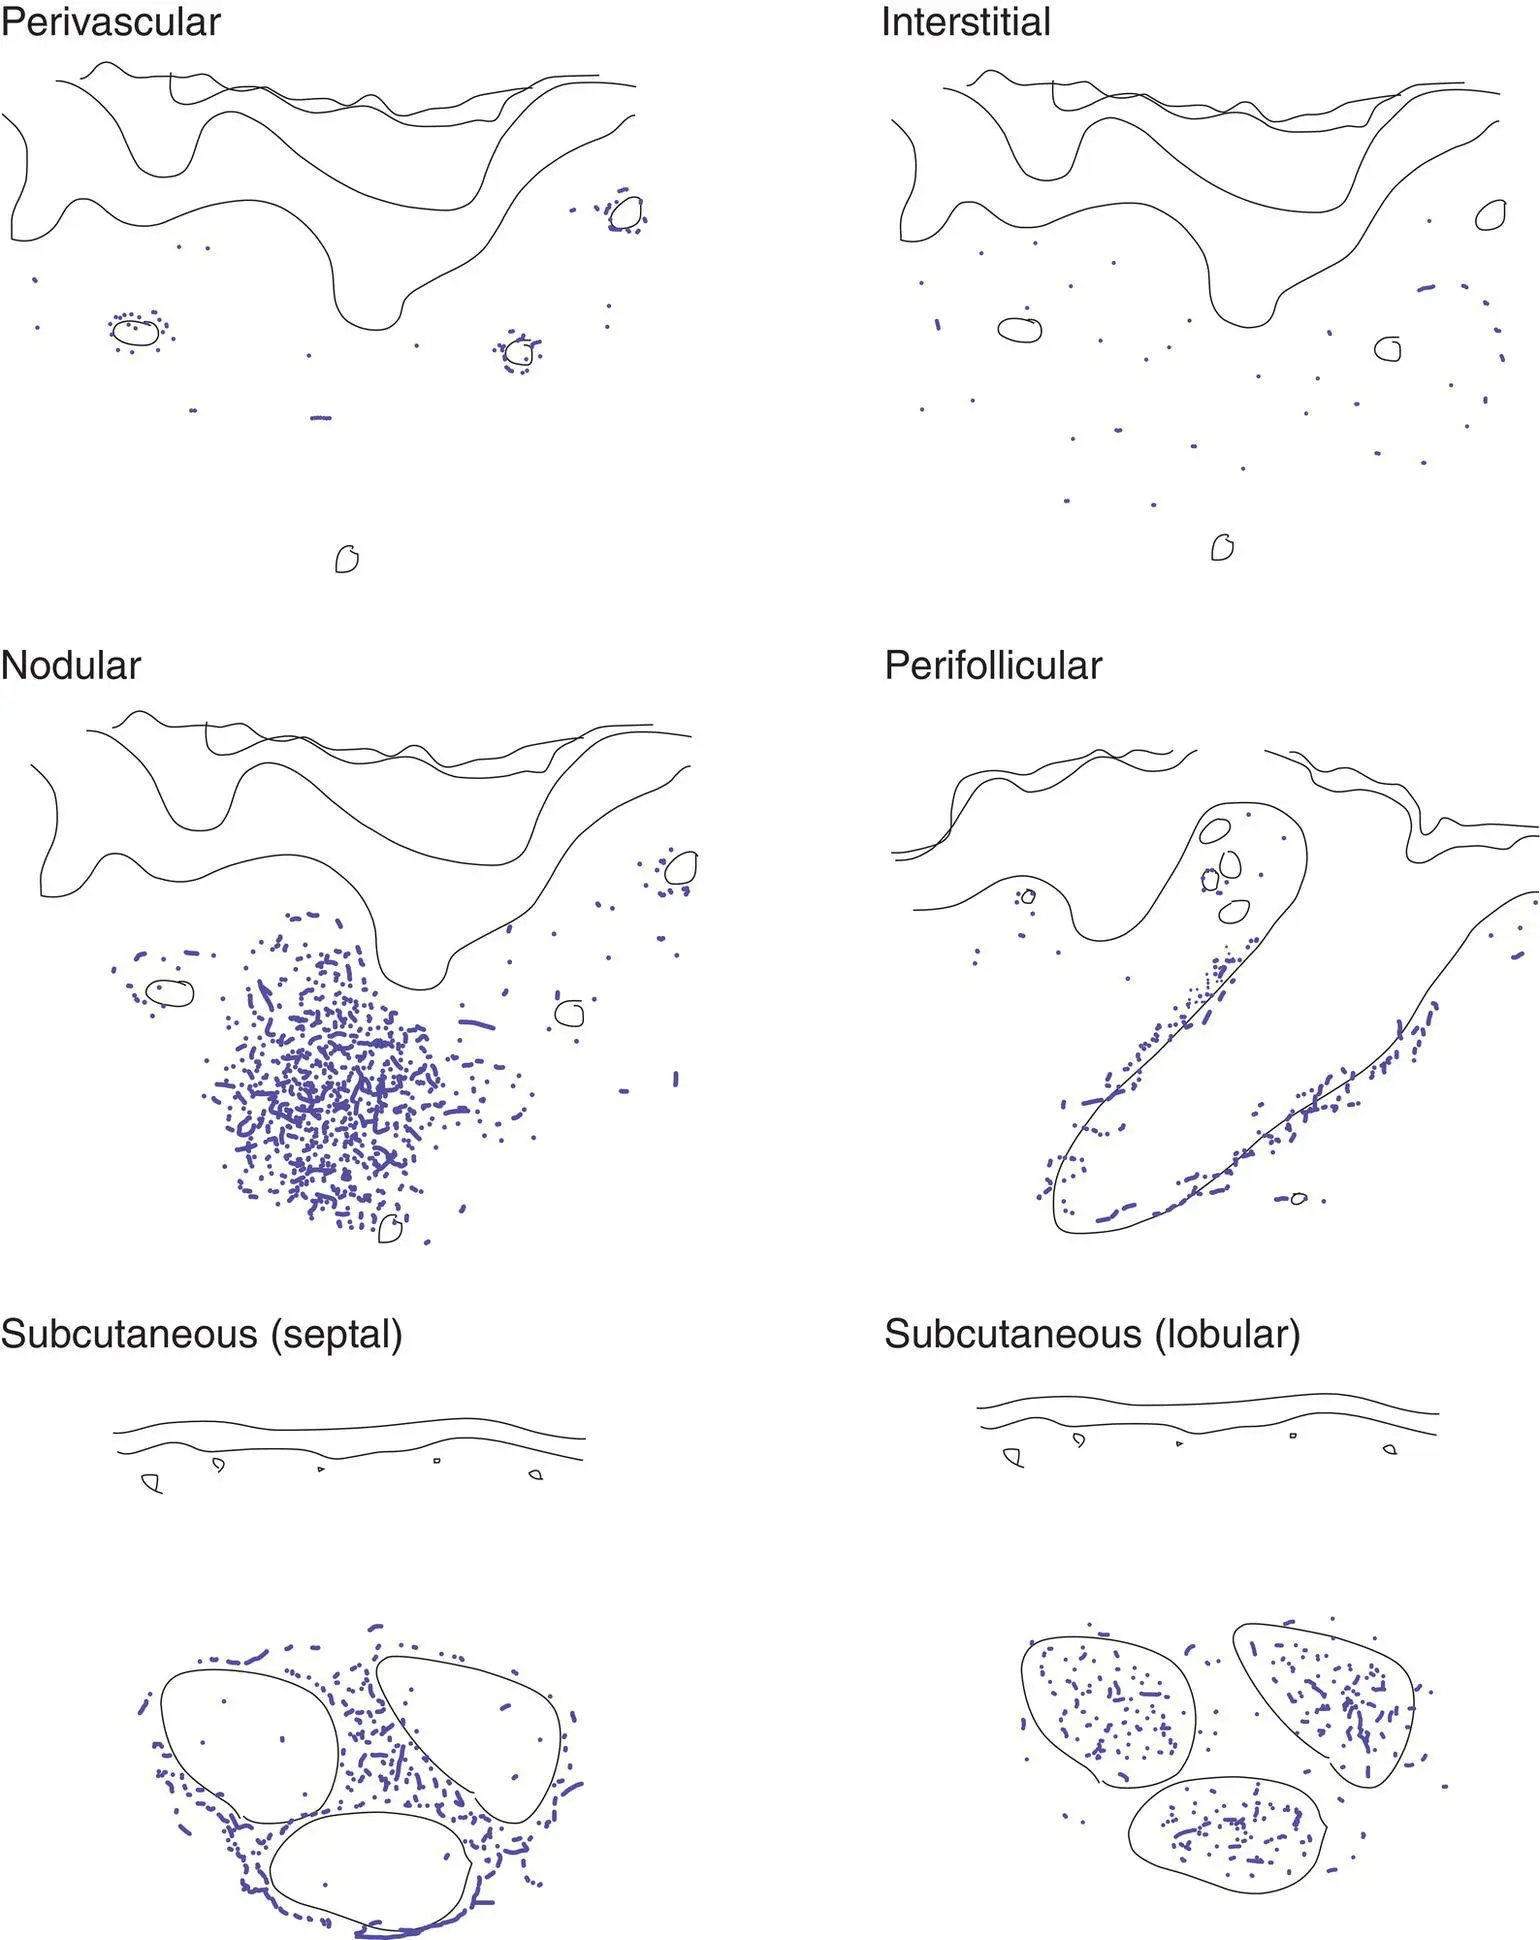

“Rash”: key concepts

The eye can be trained to focus in on the blue areas (figure–ground separation; grouping)

Key features include epidermal changes (A), distribution of inflammation (B), and inflammatory cell type (C)